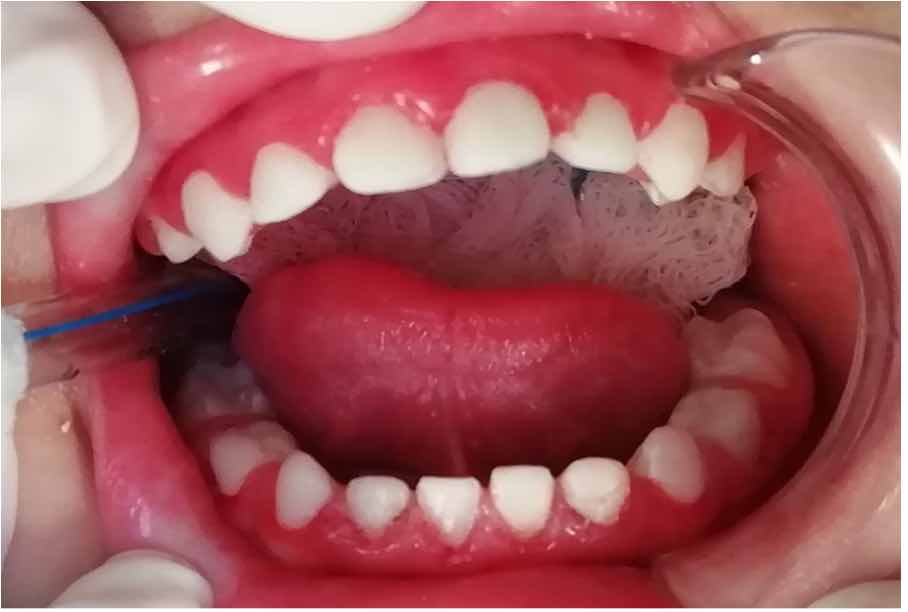

No se realizaron cambios en el plan de tratamiento, respetando la conservación de los dientes. Paciente con pronóstico favorable, ya que se trataron todos los dientes, no hubo pérdida de ninguna pieza dentaria y sobre todo por la concientización a la madre sobre el cuidado de la salud bucal de su hijo (Figura 2).

Figura 2: Rehabilitación de las fracturas post eruptivas de extensión I y II con carillas de resina compuesta fotopolimerizable en dientes 63, 73, 72, 71, 81, 82, 83 y en las fracturas post eruptivas de extensión III se realizaron pulpectomías en los dientes 52, 62, y con sus respectivas coronas de resina compuesta fotopolimerizable a mano alzada de las piezas 52, 62.

Se evaluó al paciente por medio de solo controles clínicos post operatorios, puesto que la paciente presentó nula colaboración a la toma de radiografías periapicales y panorámica. Estos controles fueron a los 7 días y a los 2 meses, no se observó desprendimientos de restauraciones, presencia de las coronas de resina y carillas de resina en boca, nivel de higiene bucal buena. Madre del paciente refirió que su hijo no presentó ninguna molestia después del tratamiento, se alimenta con normalidad, ya no presenta dolor al momento de masticar, y se citó a madre para su segundo control en dos meses. En segundo control, madre refiere que no ha tenido ningún dolor ni molestia. Al examen clínico no se observó desprendimiento de restauraciones en los dientes, se observa una encía más rosada y menos sangrante, se vuelve a dar indicaciones de higiene bucal y se citó en 6 meses. En resumen, paciente después de sus controles no evidencia signos clínicos de inflamación. A la fecha no se suscitó algún evento adverso de parte de nuestro paciente (Figura 3).

Figura 3: Control a los 6 meses.